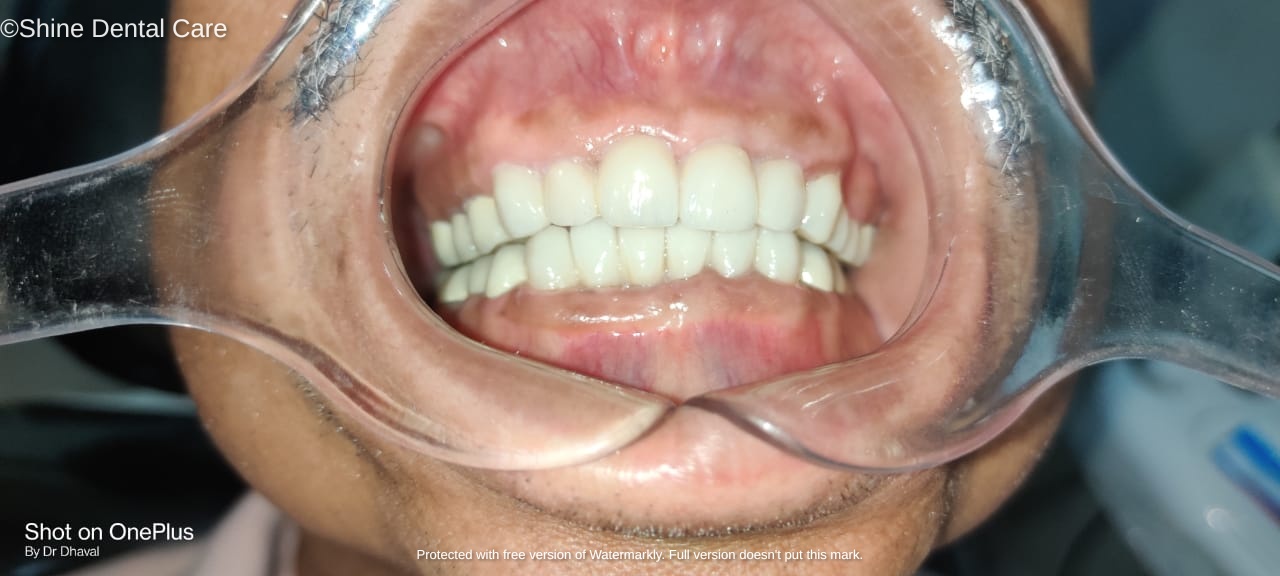

Full Mouth Rehabilitation

As the name implies, Full Mouth Rehabilitation refers to rebuilding and/or replacing all of the teeth ina patient’s mouth. Full Mouth Rehabilitations combine esthetics with the science of restorative dentistry to improve the health, function, and beauty of the mouth.

The treatments can include onlays, crowns, bridges, veneers, dental implants, and/or dentures that will essentially provide not only a "'smile makeover", but improved chewing efficiency for the patient. In some patients, other specialties will orthodontics may also be employed to facilitate the best possible outcome.